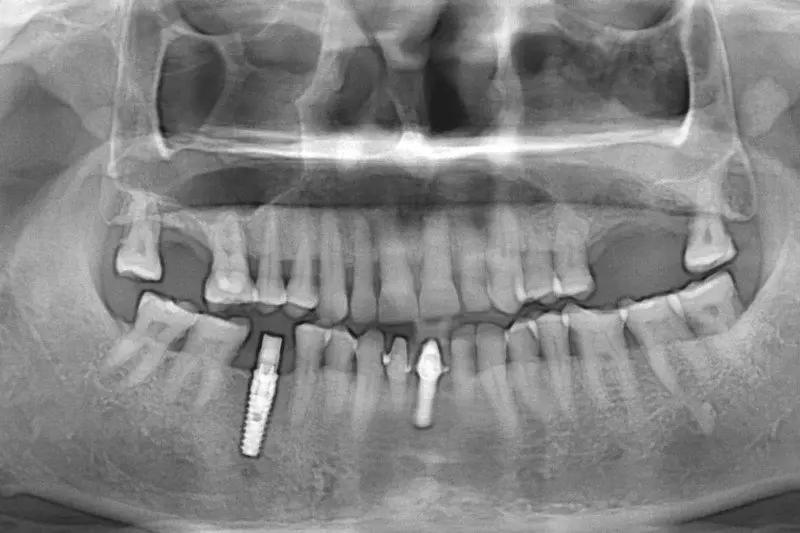

There are two types of sinus graft procedures:

[1] Indirect Sinus floor Elevation with placement of implant

[2] Direct Sinus Graft using modified caldwell luc technique

The maxillary sinuses are behind your cheeks and on the top of the upper teeth. Sinuses are like empty rooms that have nothing in them. Some of the roots of the natural upper teeth extend up in to the maxillary sinuses. When the upper teeth removed, there is often just a thin wall of bone separating the maxillary sinus and the mouth. Dental implants need bone to hold them in place. When the sinus wall is thin, it is impossible to place dental implants in this bone.

There is also a solution, its called sinus graft or sinus lift. The specialist or skilled implantologist enters the sinus from where upper teeth used to be. The thin paper like sinus membrane carefully lifted upward and donor bone is inserted into the floor of sinus. After several months of healing, the bone becomes the part of the patient’s jaw and dental implant can be inserted and stabilized in this new sinus bone.

Furthermore, If enough bone between the upper jaw ridge and the bottom of the sinus available to stabilize the implant well, sinus augmentations and implant placement can sometimes be performed as a single procedure. If enough bone is not available sinus augmentation will have to be performed first, then the graft will have to mature for several months, depending upon the type of graft material used. Once the graft material has matured, the implant can be placed.